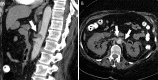

In this article we will review the imaging features of coronavirus disease 2019 (COVID-19) across multiple modalities, including radiography, CT, MRI, PET/CT, and US. Given that COVID-19 primarily affects the lung parenchyma by causing pneumonia, our directive is to focus on thoracic findings associated with COVID-19. We aim to enhance radiologists' understanding of this disease to help guide diagnosis and management. Supplemental material is available for this article. © RSNA, 2020.